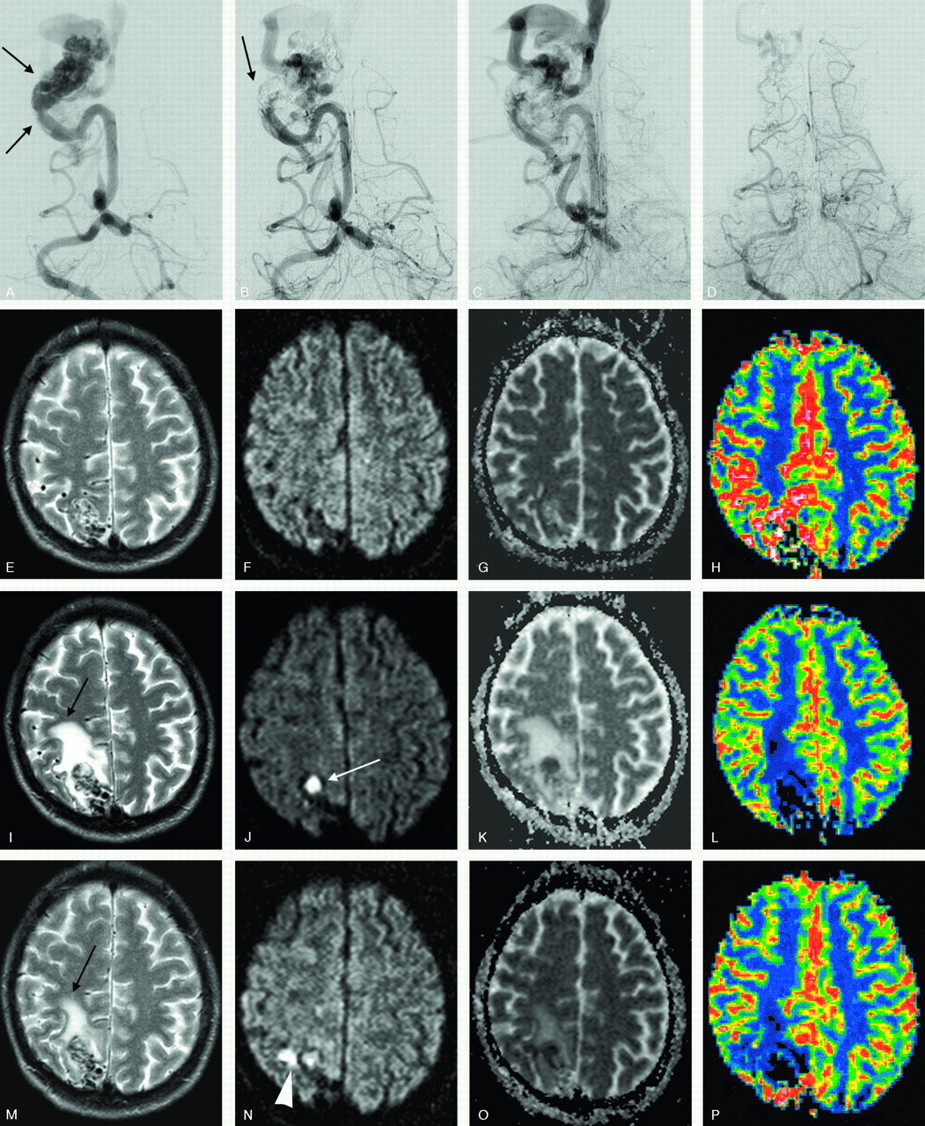

Occipital AVM before and after treatment.

A, Frontal right vertebral angiogram demonstrates a small, high-flow, parieto-occipital AVM with an enlarged feeder supplying 2 intranidal fistulas (arrows) before embolization.

B and C, Same projection after partial embolization. Glue can be seen at the site of the fistulas, and the venous drainage remained patent.

D, DSA, performed 6 weeks later (same projection) in conjunction with and before an additional embolization. A spontaneous occlusion of the feeder supplying the fistula is noted with a partial reduction of the nidus. The vein is still patent but reduced in size.

E–P, Axial T2-weighted, DWI, ADC maps, and rCBF done after the first embolization (E–H), before (I–L), and after (M–P) the second treatment. A vasogenic edema (black arrow) evolved in between the treatments, because of a spontaneous thrombosis of the feeder, nidus plus draining vein (white arrow), and decreased immediately after the second embolization. A small, perinidal ischemic lesion is seen after the last treatment (arrowhead). The patient experienced minor and transient headaches in between the embolizations.

New MR Imaging Patterns, including DWI and PI, Evolving between Procedures

New MR imaging abnormalities were noted between treatments in 3 patients. Pure progressive venous outlet thrombosis associated with an “asymptomatic” ICH (subacute hematoma in resolution) was found in one patient and a severely disturbed perfusion pattern with increased MTT in a second (Fig 4). The latter occurred contralaterally to the embolized AVM. Following a week of conservative medication therapy and regular MR imaging monitoring, PI ultimately returned to normal (see discussion below). A more extensive thrombosis involving the feeding artery, the nidus, and, in particular, the draining vein, was seen in the third patient and resulted in vasogenic edema in the white matter with a matching PI defect (Fig 5).

Vasogenic edema surrounding a draining vein was found in one patient before treatment and resolved after embolizations and shunt reduction. Although the procedures were uneventful, vasogenic edema appeared around the nidus on MR imaging immediately after treatment in 4 patients and between treatments in one patient with a progressive venous occlusion (Fig 5). Perfusion was decreased in the area of edema. The edema was initially asymptomatic in the first 4 patients. Three days later, 2 patients developed paresthesia and hemiparesis, respectively, both transient. In one of the patients, however, allodynia developed later. In each of the 2 patients, postprocedural MR imaging, including FLASH images, failed to visualize a hemorrhagic component, though a minor hematoma organized around the AVM nidus was revealed on CT performed 2 days later (Fig 3). However, the virtually identical appearances of the susceptibility artifacts generated by glue and hemorrhage may explain the failure of FLASH sequences to identify the hemorrhage.

The vasogenic edema may also have reflected a minimal vascular tear with a slowly progressing hemorrhage that initially went unnoticed. Alternatively, it may have served as a precursor for hemorrhage. Three patients with vasogenic edema did not show any bleeding. In all 5 patients, a minimal volume of glue had entered into the draining veins of the AVM. The immediate postprocedural DSA showed no interference with the venous drainage, though in one case the dominant draining vein was not opacified afterward. We believe that vasogenic edema may be caused by venous congestion with or without venous thrombosis and that it may be associated with an increased risk of hemorrhage, especially in high-flow AVMs.57